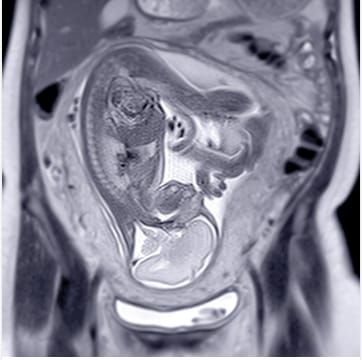

Pediatric Body MRI 2015 (Videos) is designed to help radiologists become familiar with current state-of-the-art body MR imaging techniques, the practical applications of these techniques, and the key MR imaging features of a wide array of disease processes in children. The goal of the program is to help pediatric radiologists, general radiologists and MRI technologists continually improve clinical performance and pediatric health care through the proper application MR imaging techniques and to better understand the role of body MRI in the management and treatment of pediatric diseases. It will help you to better:

Female Pelvis: Congenital Anomalies - Jesse Courtier, MD

Female Pelvis: Acquired Abnormalities Including Tumors - Monica Epelman, MD